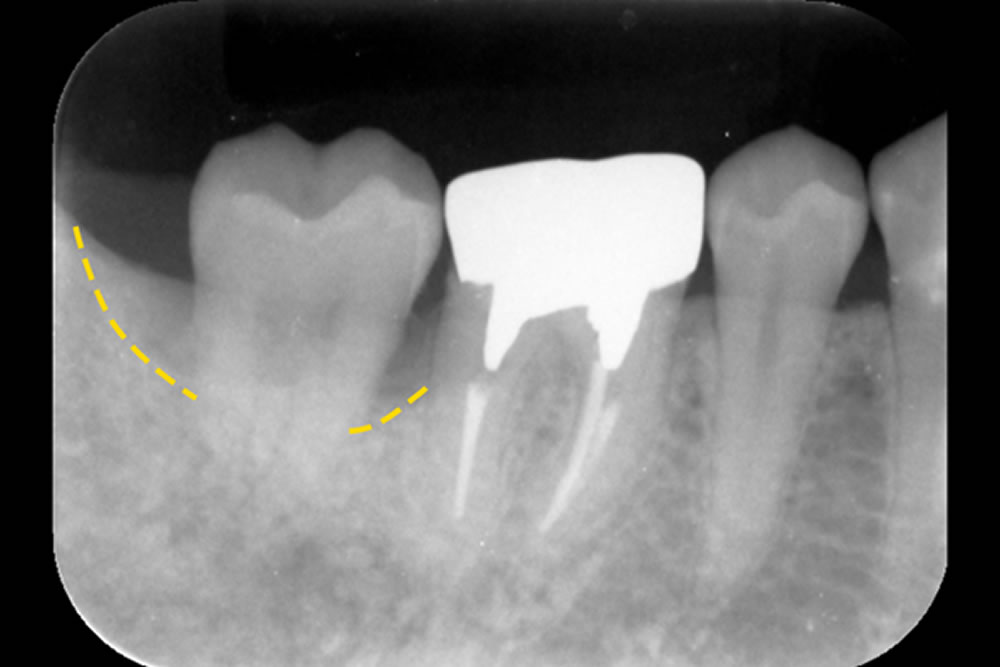

- 3.1 重症化した歯周病を手術なしで治療した症例

- 3.2 グラグラする歯を手術なしで治療した症例

- 3.3 他院で抜歯と診断された歯を手術なしで治療した症例

- 3.4 骨を部分的に欠損した歯を手術なしで改善した症例

まずは、論より証拠。日本歯周病学会専門医である当院の院長が実際に行った「重度歯周病で抜くことになる確率が高い歯を抜かなかった歯周病改善例」をご紹介します。

初診時(上写真)、右下6番目の歯は今にも抜け落ちそうな状態でしたが、重度歯周病治療【MINST】によって、症状を改善し、術後1年後(下写真)には歯周組織もしっかりと再生しました。

※外科処置なし・再生材料も使用しておりません。